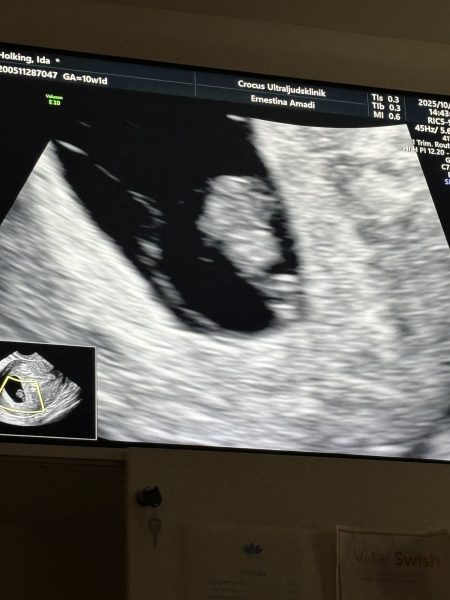

Idag går Ida in i vecka 9, igår hade hon ytterligare ett ultraljud där vi fick se det lilla hjärtat slå ❤️